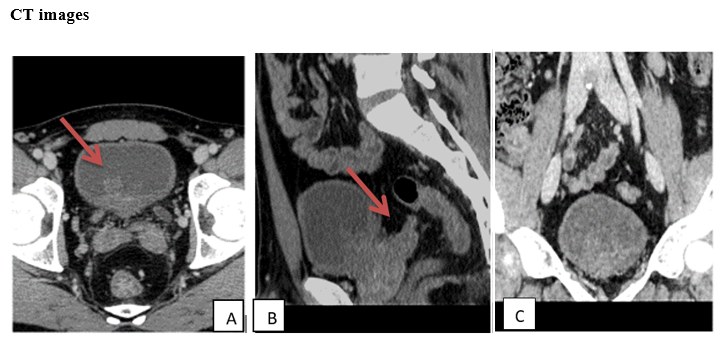

Under the microscope, these lesions can manifest as either a single layer of mucus-producing goblet cells, resembling the mucosa of the large bowel, or as multilayered mucus-producing cells that resemble normal prostatic glands. Both cell types have been identified in both the bladder dome and trigone area.7 (Figure 2)

Figure 2 Under the microscope, these lesions exhibit a single layer of mucus-producing goblet cells.